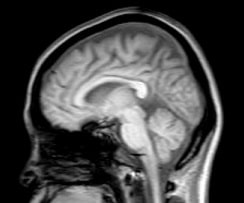

脳や脊髄神経は脳脊髄液につつまれています。脳脊髄液は絶えず循環していれかわっています。

脳脊髄液は頭蓋骨と頸椎でつくる関節、腰椎と仙骨でつくる関節のポンプ作用などによって循環が促されているといわれています。

脳脊髄液の循環が低下すると、脳や脊髄、それらを覆う脳膜や脊髄膜の代謝が低下するので、免疫力が下がり脳膜炎や髄膜炎などのさまざまな問題が生じやすくなることが考えられます。